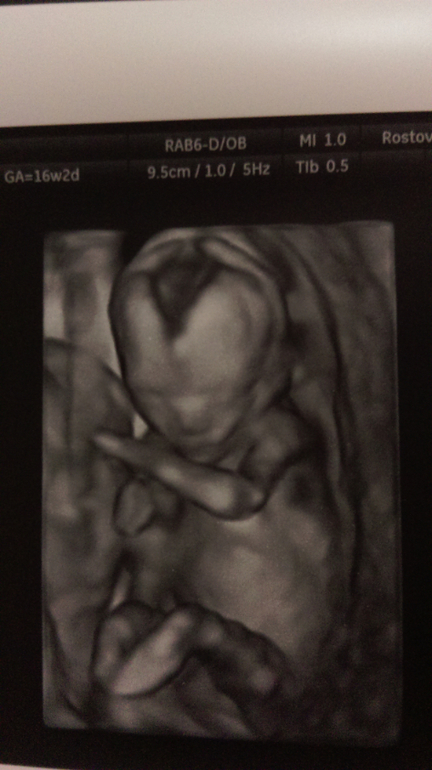

В четверг была на УЗИ. Мои внутренние ощущения оправдались - это девочка!!! Надеюсь, что будет без сюрпризов )))

По УЗИ все в норме, вес 150г уже примерно.

Сделали несколько фотографий, я их очень ждала, чтобы дочке их показать и рассказать, но до сих пор этого не сделала... Прошлые страхи дают о себе знать...

Следующее контрольное УЗИ аж 5 декабря! Очень жду его!!! Все будет хорошо, я верю!!!